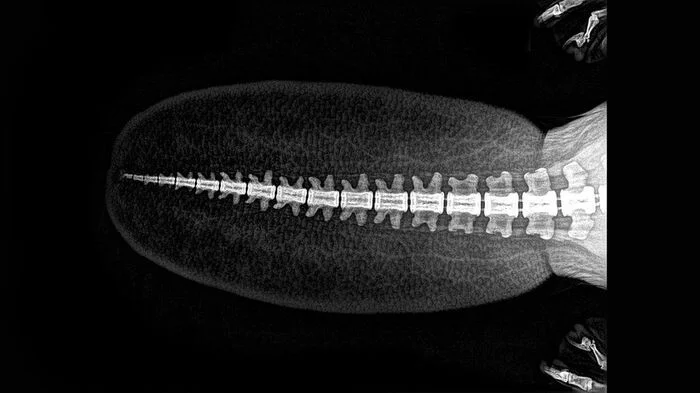

13. Хвост бобра

Таким снимком поделился зоопарк в Орегоне, США. Кроме бобра сотрудники показали и то, как на рентгене выглядят другие зверюшки.